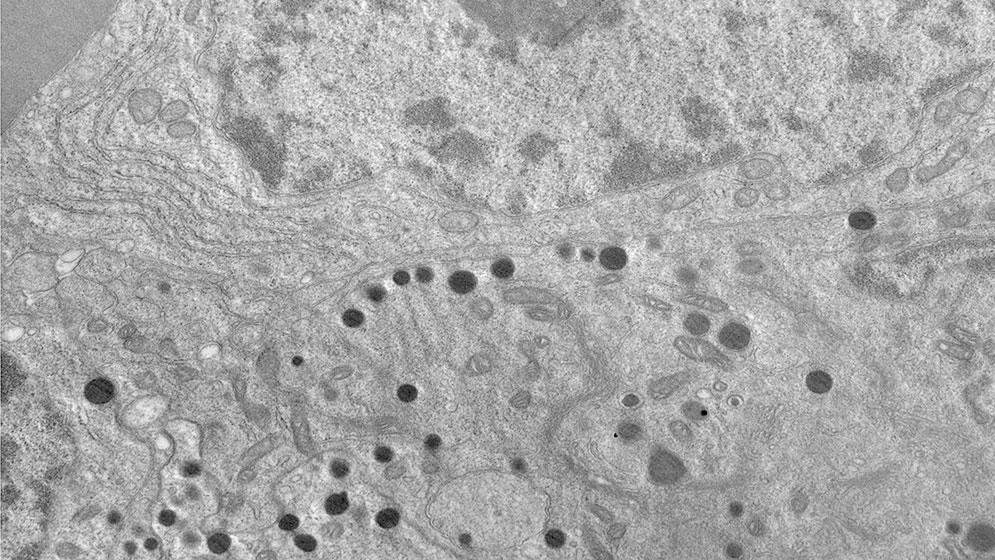

Genetista misionera integra una novedosa investigación para tratar tumores cerebrales. Se trata de Gilda Florencia Mezger, licenciada en Genética egresada de la Universidad Nacional de Misiones (UNaM), forma parte del equipo interdisciplinario del INICSA (CONICET-UNC) y del Hospital Privado Universitario de Córdoba que acaba de lograr un avance significativo en la investigación oncológica. Se trata de la identificación de un nuevo blanco terapéutico para tratar tumores hipofisarios, un tipo de tumor intracraneal cuya complejidad representa un gran desafío para la medicina actual.

El avance científico, recientemente difundido, se centra en el descubrimiento de una proteína llamada SHP2, que actúa como un nuevo blanco terapéutico. La inhibición de esta proteína logró frenar el crecimiento tumoral en ensayos preclínicos realizados en ratones.

El descubrimiento no significa que ya haya una cura definitiva, pero sí marca un paso firme hacia nuevos tratamientos: “Se probó ya en un modelo in vivo y se observó una disminución del tumor. Aún faltan muchas etapas: ensayos más grandes, aprobación de comités de ética, y luego el desarrollo farmacológico”, advierte Gilda, con la cautela propia del método científico.